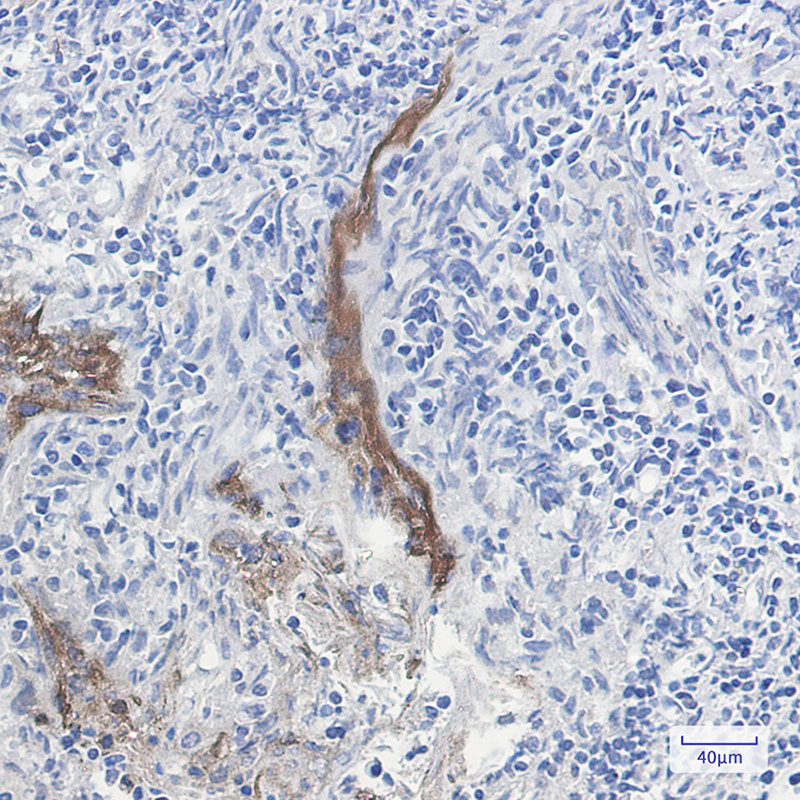

Immunohistochemistry analysis of paraffin-embedded Human tonsil using Extracellular matrix protein 1 antibody. High-pressure and temperature Sodium Citrate pH 6.0 was used for antigen retrieval.